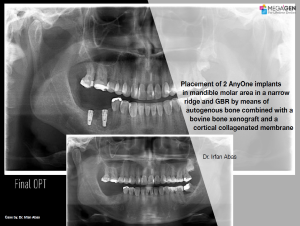

Aesthetic zone,AnyRidge,Clinical case,Dr. Achraf Souayah,Edentulous,Guided surgery,Immediate Placement,Mandibular Anterior,Mandibular Posterior,Maxillary Anterior,Maxillary Posterior,MEG-Rhein,MILA Kit,Overdenture system,Sinus Elevation